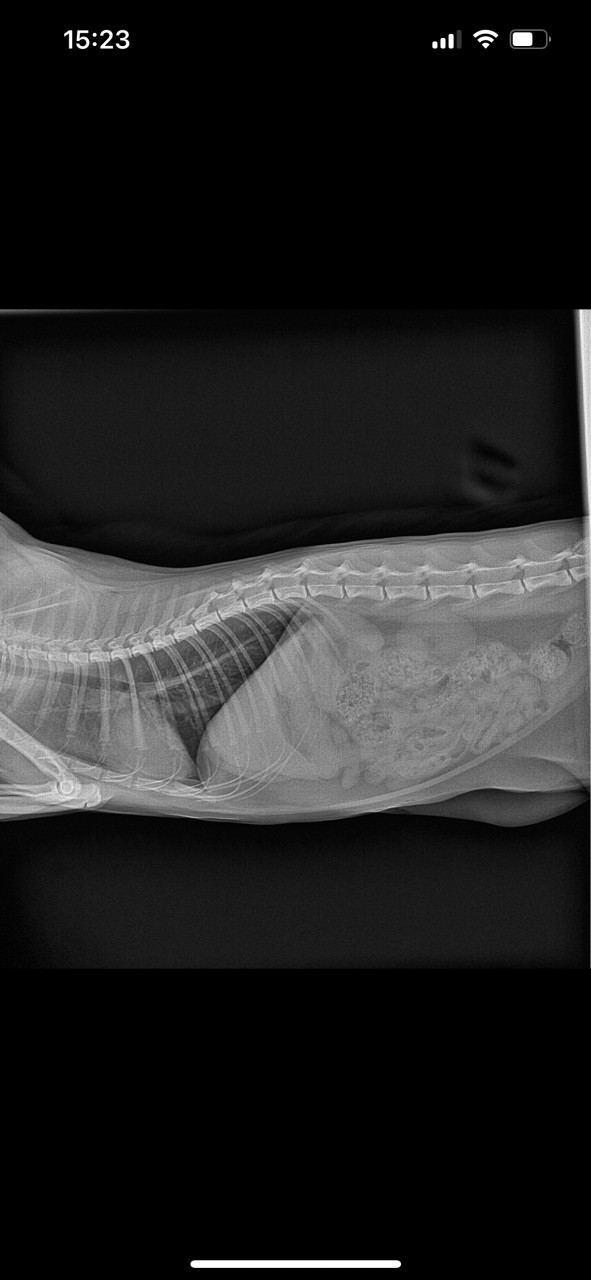

Посмотрите пожалуйста рентген все ли в порядке

Здравствуйте. По представленным рентгеновским снимкам грудной клетки кота визуализируются уплотнённые бронхи и выраженный бронхолёгочный рисунок, что может свидетельствовать о хроническом бронхите, астмоидном синдроме или воспалении дыхательных путей. Сердце и диафрагма выглядят без грубых отклонений, но для точной оценки необходимо заключение ветеринарного рентгенолога. Хрипы у кота  это не норма, особенно при хроническом течении. Обратитесь к ветеринару для назначения терапии.